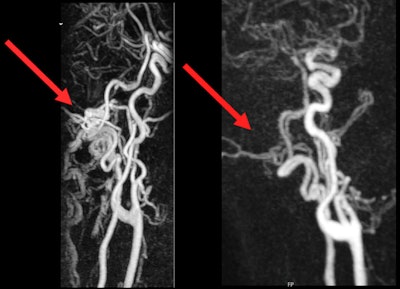

(Left) MRI before intervention. Pathological flow signal in the area of the left occipital condyle can be seen. (Right) MRI after intervention. No more pathological flow signal, and the tinnitus is visible.Images courtesy of UKE Hamburg-Eppendorf and Dr. Fabian Flottmann.

It can be diagnosed using techniques such as contrast-enhanced MRI, time-resolved MR angiography, and CT or catheter angiography to precisely localize vascular changes. In many cases, it can then be causally treated, he explained.

Procedures for pulse-synchronous tinnitus are usually minimally invasive and performed via the wrist artery or the inguinal artery. Fistulas may be treated with embolizations, in which the "short circuit" between the artery and vein is closed with platinum coils or tissue adhesive; constrictions in venous drainage pathways may be widened using stents.